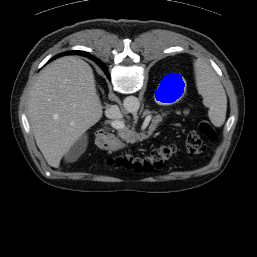

Support

Label

Proposed

In order to assess the performance of the proposed method, we compare the performance of the proposed model with excellent models in recent years. Table 1 and Table 2 shows the comparison results of different models in setting1, while Table 3 and Table 4 shows the comparison results of different models in setting2 on the data set in recent years. PANet[25] is the most widely influential few-shot model in the field of few-shot image segmentation on natural images. SENet [18] is the first few-shot segmentation model proposed for medical images. SSL-ALPNet[19] introduced the milestone of using superpixel self-supervision to train few-shot medical image models. RPNet[29] is a supervised method with a recursive mask optimization module to iteratively optimize the segmentation mask, [27] adapt it into the same self-supervision learning framework and applies setting1 to it and denoted as SSL-RPNet; CRAPNet[27] is the latest SOTA model for 2023. Compared with CRAPNet, our method outperforms most of the state-of-the-art models and only slightly outperforms CRAPNet. Figures 3 and 4 show examples of the model’s segmentation predictions on different datasets, respectively; The first row is the support map, the second row is the label map, and the third row is the segmentation prediction of the model.